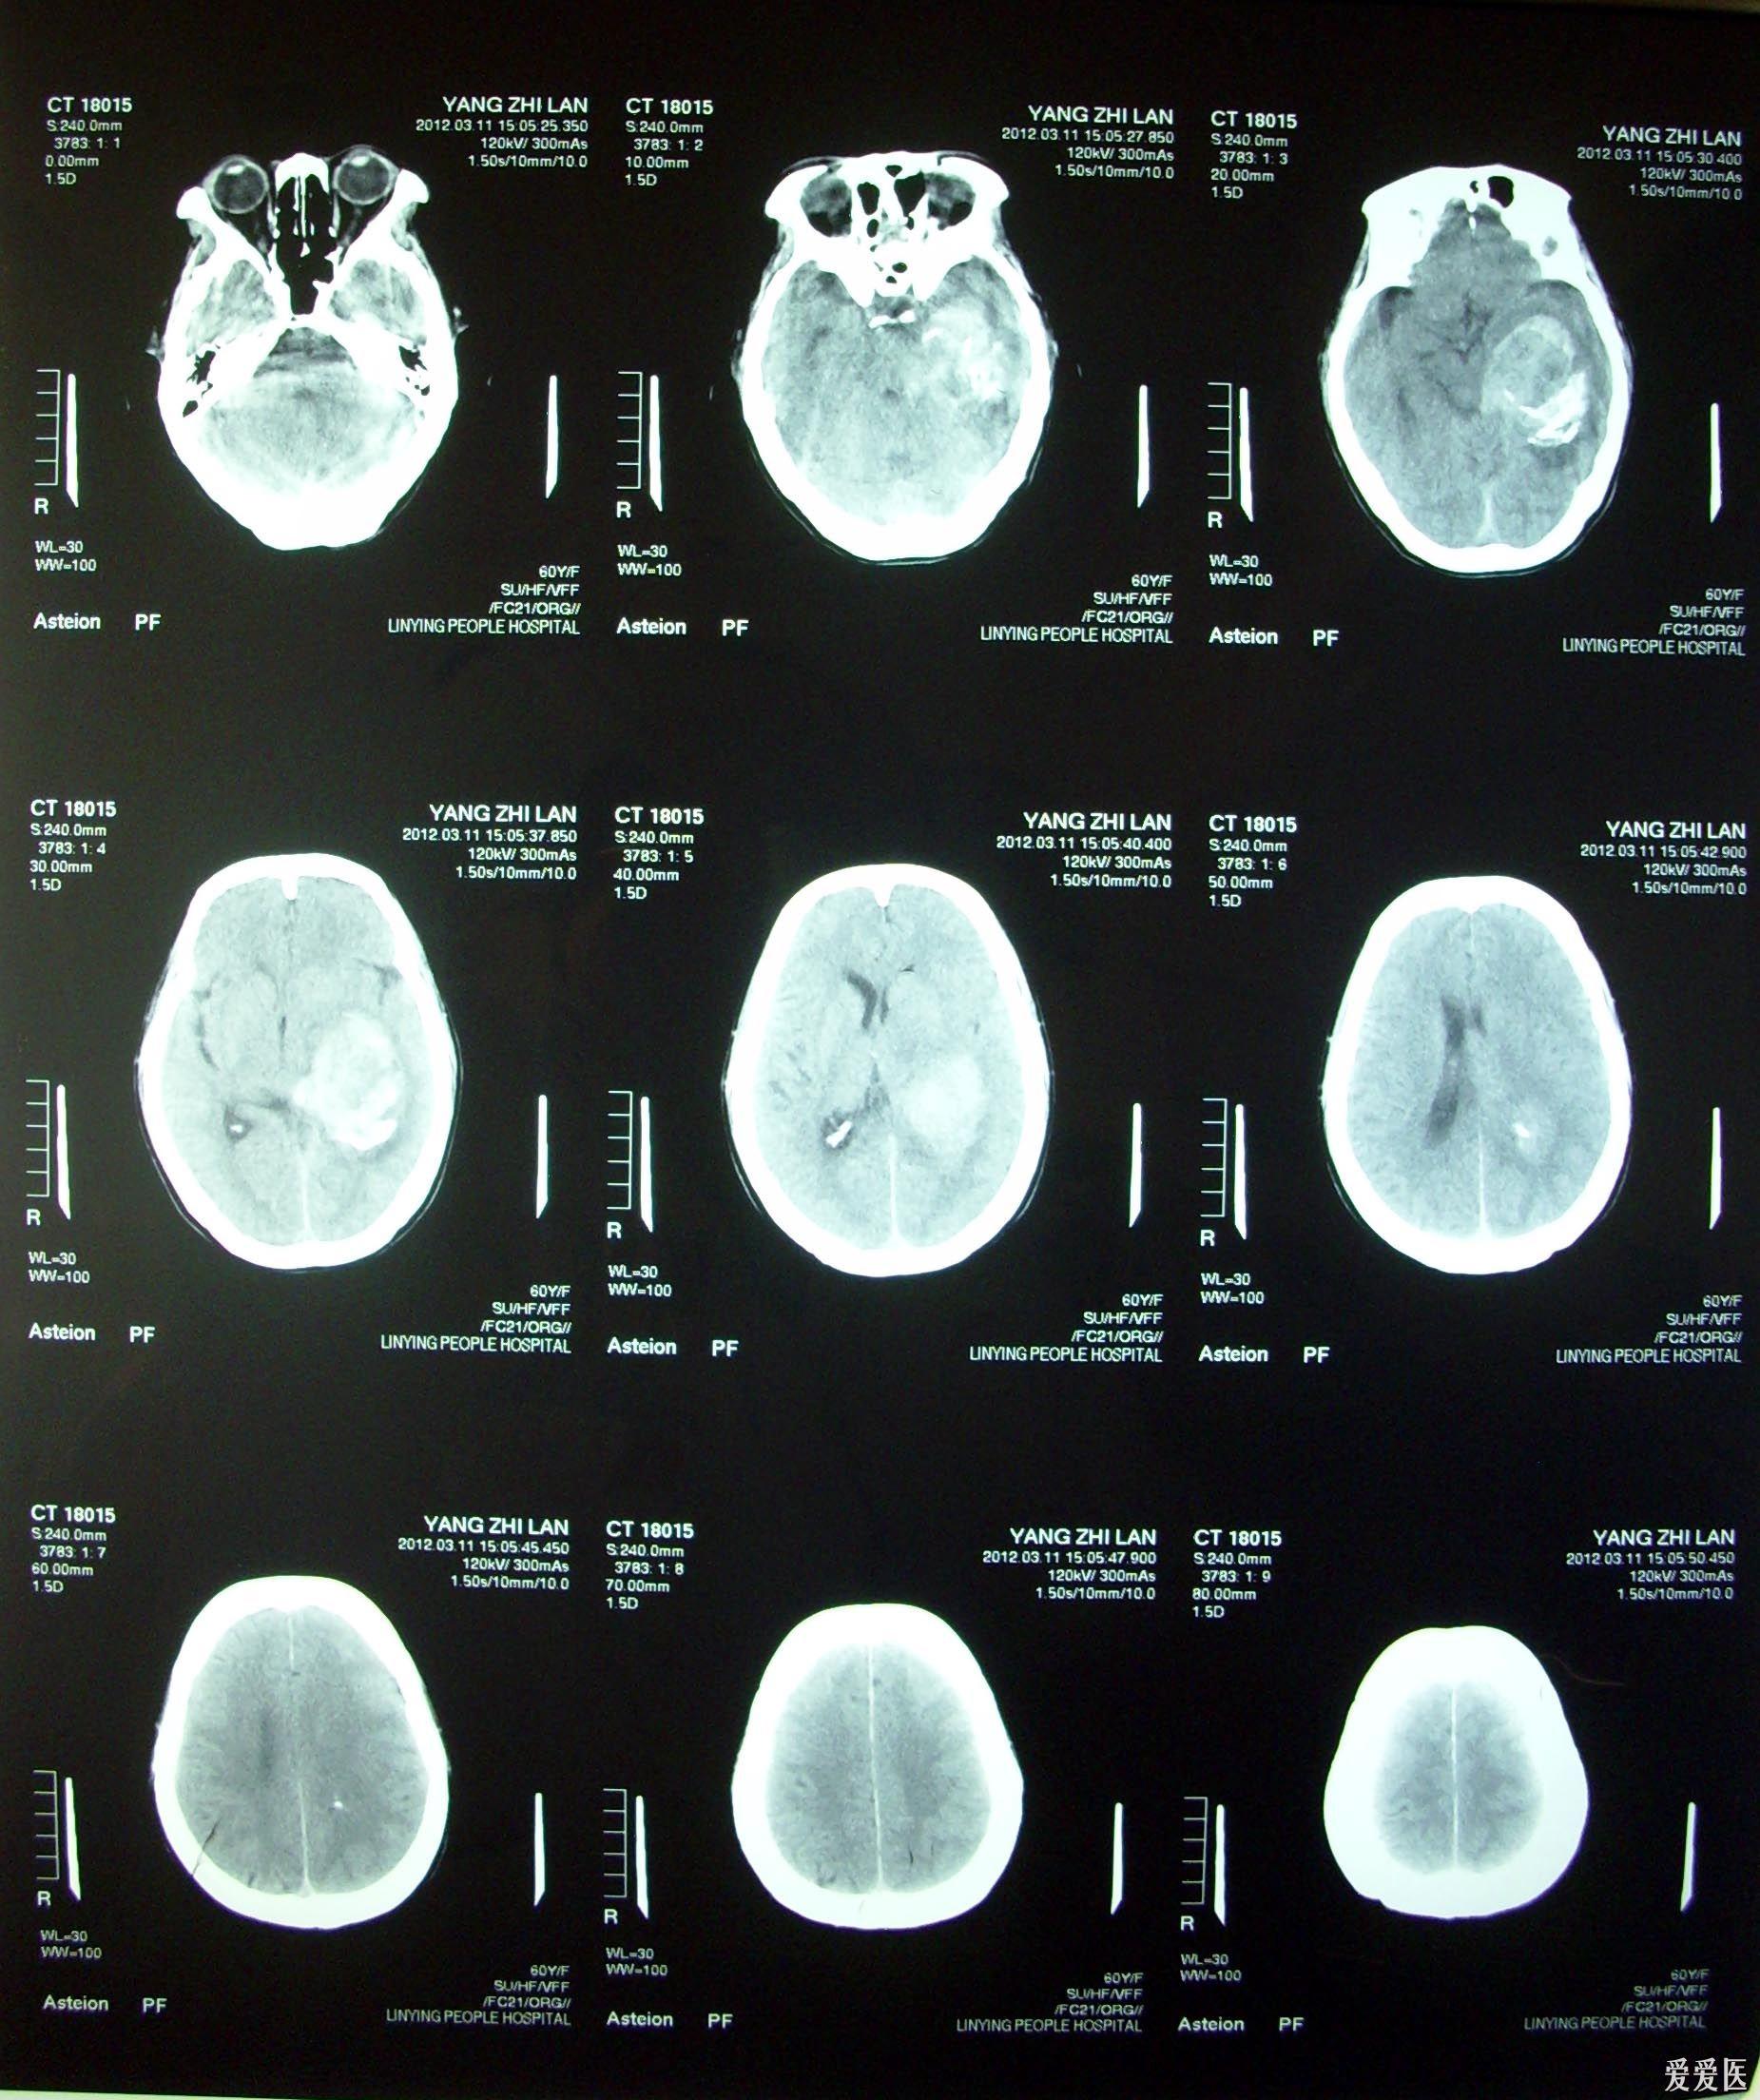

王成丽,女,58岁,右侧颞叶出血

图片尺寸3224x2165